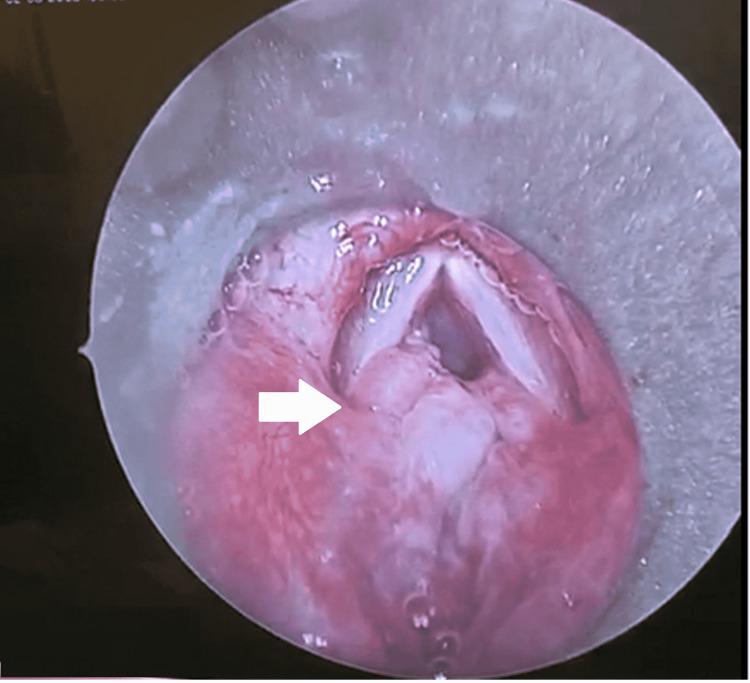

The larynx and the remaining components of the upper aerodigestive tract collectively play an important role in undertaking respiration, phonation, and deglutition. Therefore, a variety of pathologies can present with similar symptoms. Systemic diseases, such as rheumatoid arthritis and relapsing polychondritis, may also manifest with laryngeal symptoms and findings, whereas rare pathologies may present with vague presentations. Such scenarios may be attributed to the consequent medical confusion and dilemma in reaching an accurate diagnosis. In this case report, an 11-year-old male presented with airway compromise symptoms, which were later identified and diagnosed as laryngeal embryonal rhabdomyosarcoma.

喉以及上呼吸道消化道的其余部分在呼吸、发声和吞咽过程中共同发挥着重要作用。因此,多种病理状况可能表现出相似的症状。一些全身性疾病,如类风湿性关节炎和复发性多软骨炎,也可能表现出喉部症状和体征,而罕见的病理状况可能表现得较为隐匿。这种情况可能会导致在做出准确诊断时出现医疗上的困惑和两难境地。在本病例报告中,一名11岁男性出现气道受压症状,后来被确诊为喉部胚胎性横纹肌肉瘤。